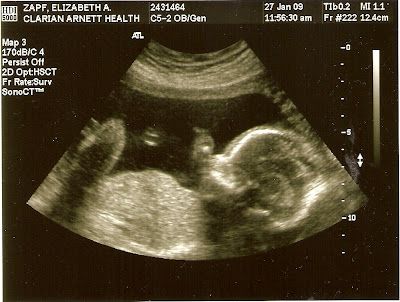

So, here is “New Baby” at 20 weeks:

I didn’t add any captions because the ultrasound tech did such a lovely job of it, I didn’t want to attempt to out-do her.